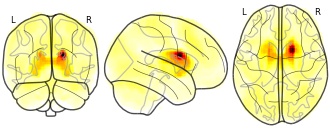

pnajdz's temporary collection: R Caudate Head 18_6_20

EmailClick to copy linkLink copied Cite(2019). pnajdz's temporary collection: R Caudate Head 18_6_20 [Dataset]. http://identifiers.org/neurovault.image:295228Unique identifierhttps://identifiers.org/neurovault.image:295228Dataset updatedOct 3, 2019License

Cite(2019). pnajdz's temporary collection: R Caudate Head 18_6_20 [Dataset]. http://identifiers.org/neurovault.image:295228Unique identifierhttps://identifiers.org/neurovault.image:295228Dataset updatedOct 3, 2019LicenseCC0 1.0 Universal Public Domain Dedicationhttps://creativecommons.org/publicdomain/zero/1.0/

License information was derived automaticallyDescriptionCollection description

None

Subject species

homo sapiens

Modality

fMRI-BOLD

Cognitive paradigm (task)

rest eyes open

Map type

Z